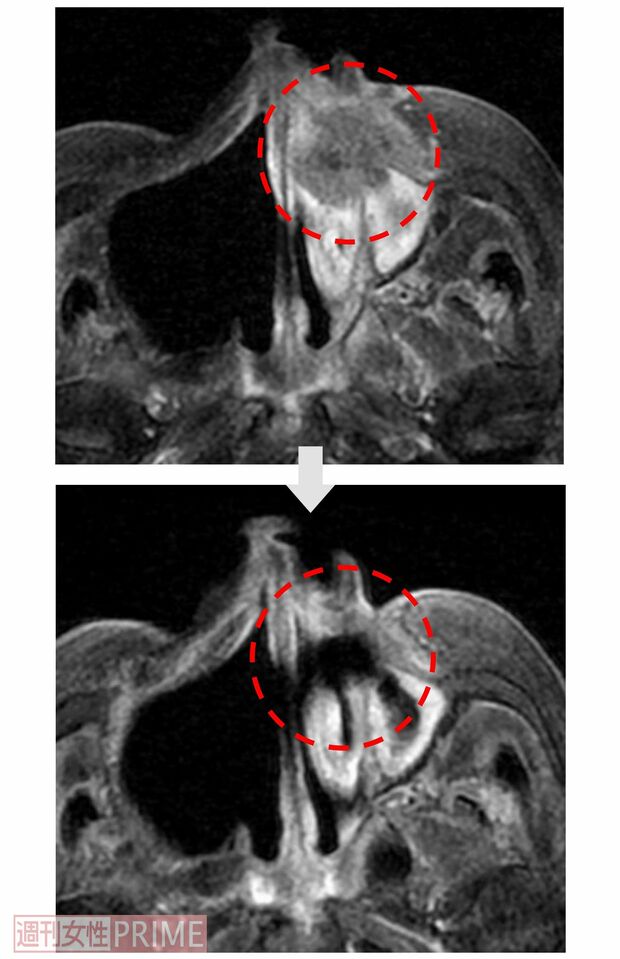

【症例2:80代女性 上顎歯肉がん】BNCT治療前後の画像

[写真 9/10枚目] 【症例2:80代女性 上顎歯肉がん】BNCT治療前後の画像